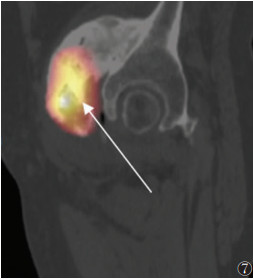

晚期病变21例,X线(21例)、CT(15例)、MRI(11例)及SPECT/CT(15例)阳性率均为100.0%。X线或CT表现为软组织内团状密度增高影,边界清晰,其中9例与相邻骨骼相连,与皮质分界不清,但髓腔不受累。MRI表现为肿块内广泛的T1WI高信号、T2WI低信号(骨化),9例病灶内含T1WI等信号、T2WI高信号、STIR低信号影(脂肪)(图 5)。SEPCT/CT显像15例,其中3例病灶中央及周围均未见显像剂摄取(图 6);6例病灶中央显像剂不均匀摄取(图 7);6例病灶周围显像剂不均匀摄取(图 8)。

| 图 7 男,48岁,右髋关节骨化性肌炎(晚期)。SPECT/CT矢状位融合图像,显示右侧髋关节骨化性肌炎病灶中央显像剂异常摄取,周围未见明显摄取(箭头) |

3.3 晚期外伤后5~6个月,肿块开始收缩,周围水肿减轻乃至消失,此期影像学诊断相对容易。X线或CT表现为边界清晰的团块状骨化,可与相邻骨骼相连,与皮质分界不清,但髓腔不受累;MRI表现为肿块内广泛的双低信号,其内可含脂肪信号。但本研究中晚期患者的SPECT/CT特征不一致,可表现为病灶完全无显像剂摄取或病灶中央显像剂高摄取而周围无摄取,也可能表现为中央无显像剂摄取而周围高摄取。提示骨化性肌炎的骨化可能是一个复杂的过程,具体机制有待进一步研究。